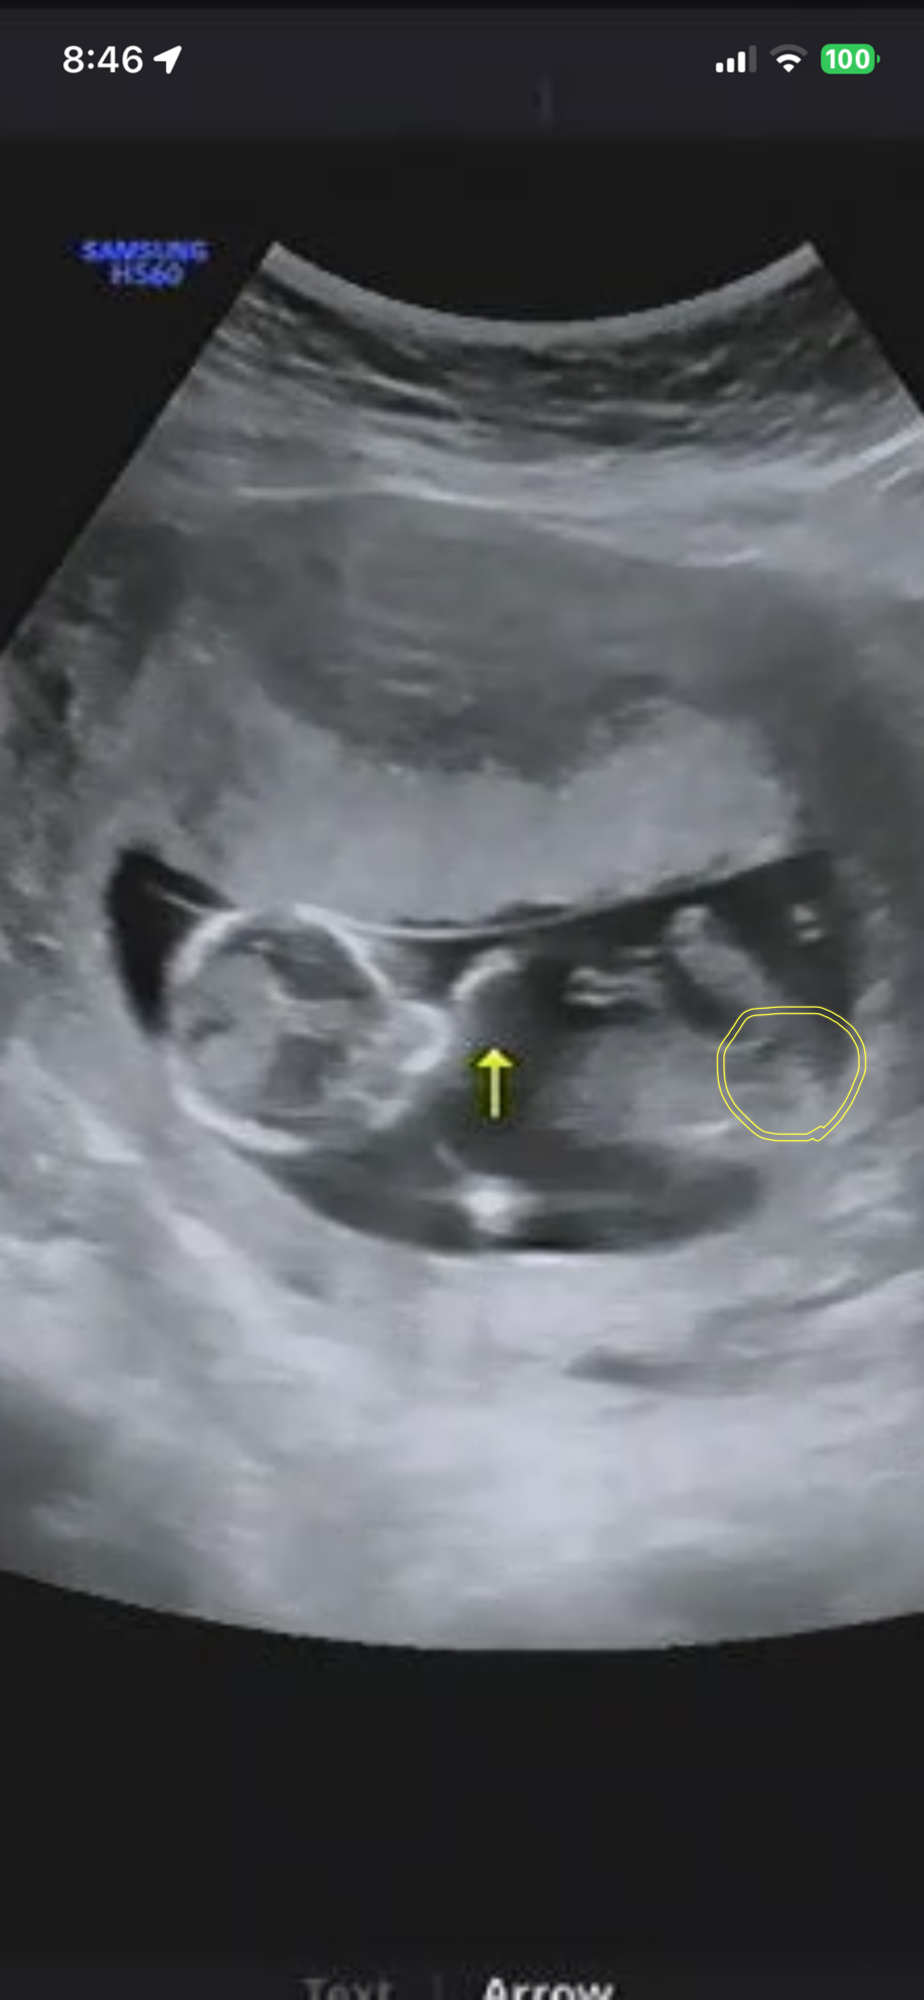

여아같아보이는데 아닌가요? 어떻게생각하시나요? 투표좀요